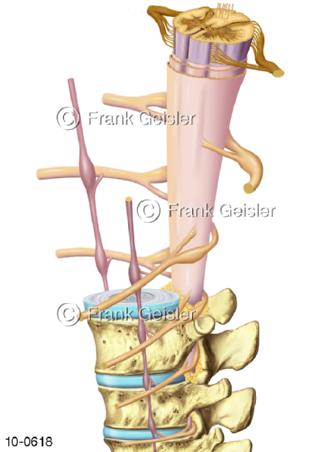

Bildergalerie Nervensystem

Bilder zum Nervensystem,dem Gehirn, Teil des zentralen Nervensystem, Zentralnervensystem ZNSmit Rückenmark, Abbildungen zum Nervengeflecht (Nervenplexus), die Verflechtungen von Nervenfasern, aus der Wirbelsäule hervortretende Nervenäst sowie Nervenzellen der Nerven